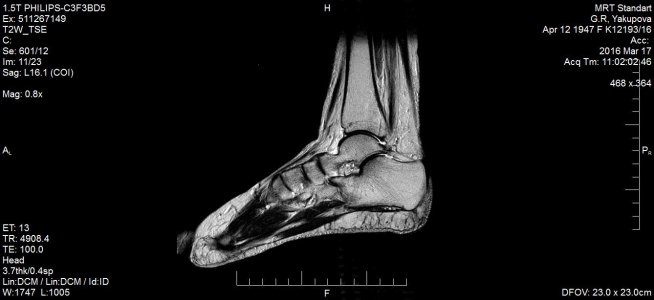

16 марта МРТ заключение: МР- картина консолидирующегося краевого косого перелома дорзальных отделов медиальной лодыжки /без смещения - перелом пилона тип В1 по АО/; остеоартроза голеностопного сустава и стопы: минимального синовита голеностопного сустава. Признаки отека мягких тканей области голеностопного сустава. (фото № 2)